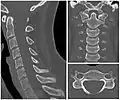

Cervical lines are annotations used in medical imaging of the cervical vertebrae, here seen on X-ray and CT, respectively. Incongruencies indicate cervical fracture, spondylolisthesis and/or ligament injury.